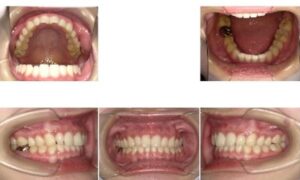

① 顔貌(顔)・口腔内写真